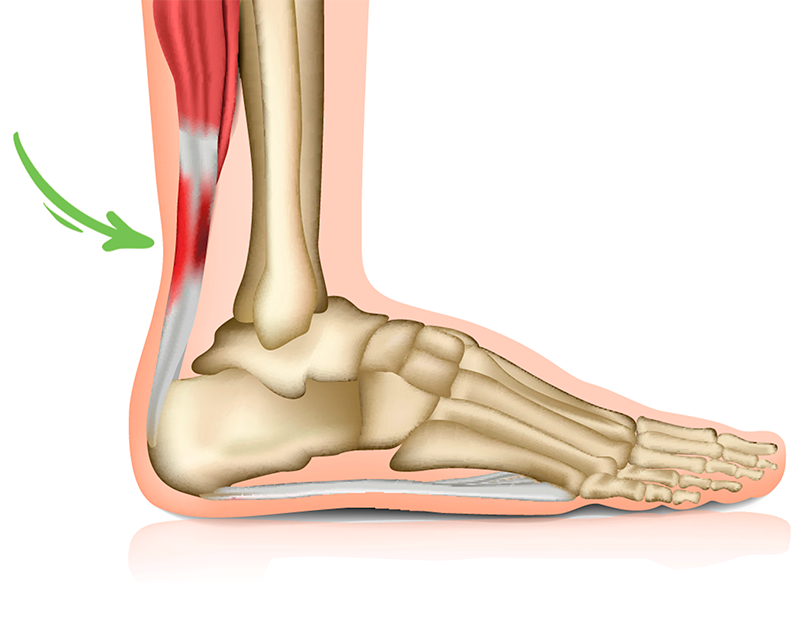

- Overbelastet akillessene